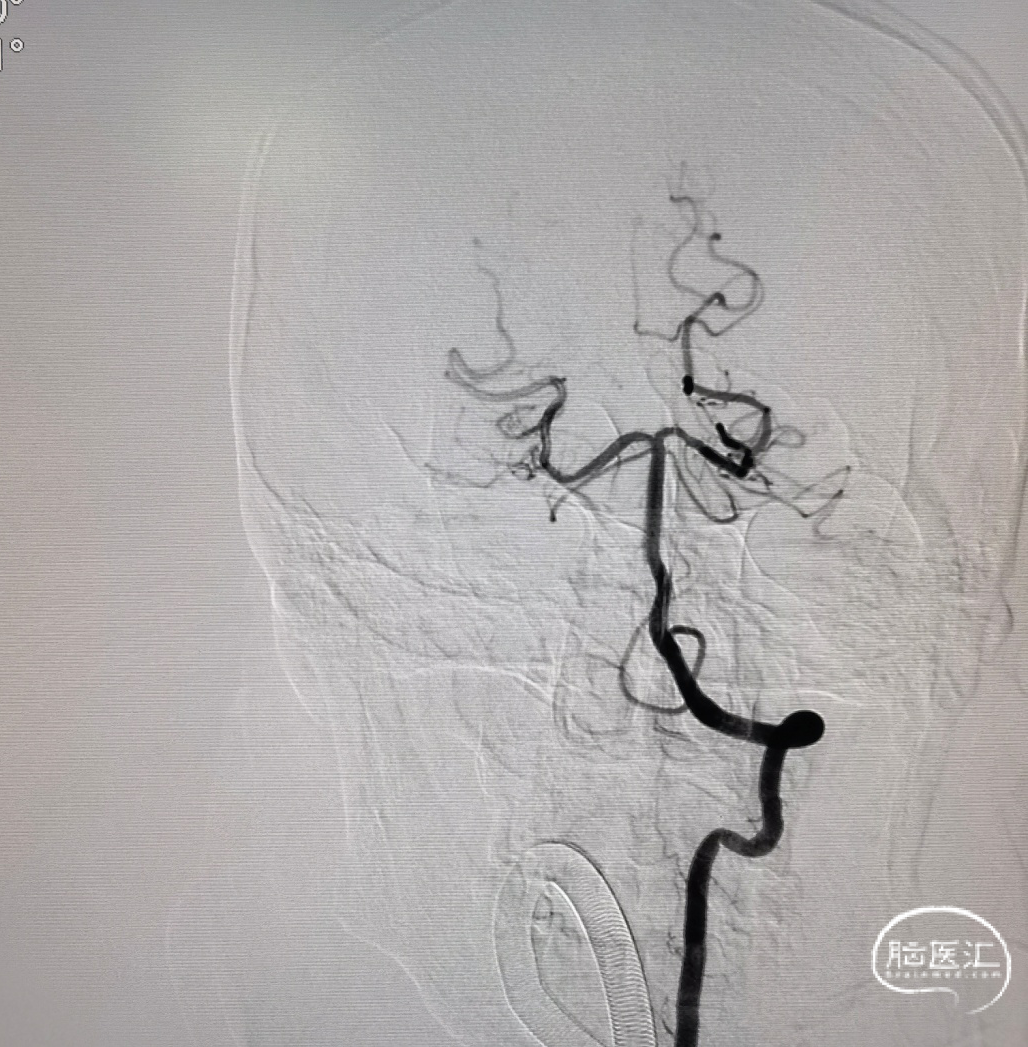

右侧颈总正侧位:见右侧颈内动脉闭塞,颅外血管代偿良好。

左椎正侧位:椎基底动脉未见异常,可见部分代偿。

左颈总正侧位:左侧颈内动脉闭塞,可见血管残端。